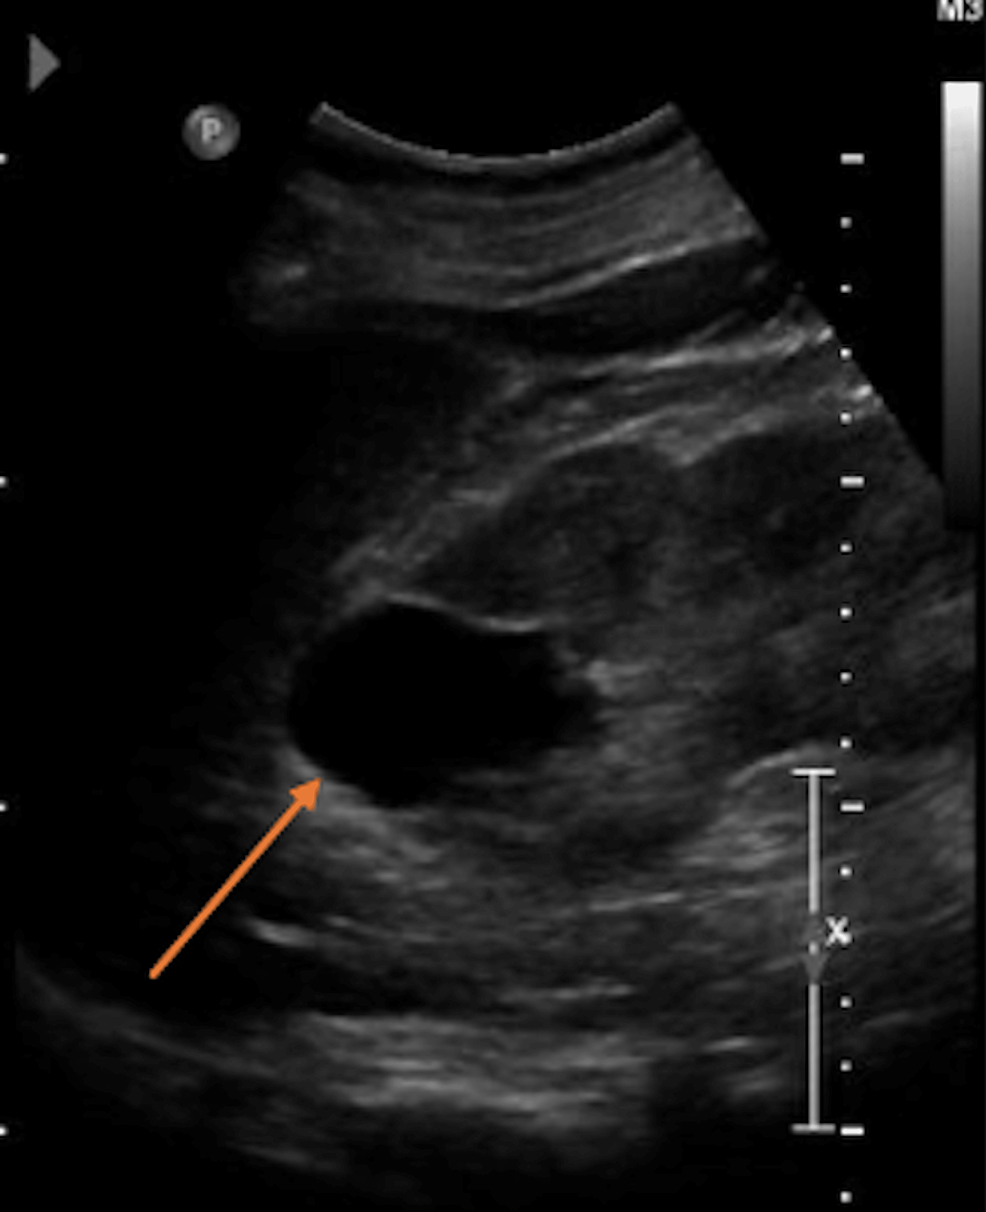

Ultrasound follow‐up eight weeks after delivery. The maximal diameter

Ultrasound follow‐up eight weeks after delivery. The maximal diameter Internal Ultrasound Showed Nothing The most common reasons for a pregnancy not. If the gestational sac —which encloses the developing baby and contains amniotic fluid—isn't visible. There is usually nothing visible on scan if you are still in early pregnancy.around 5 weeks. Is your ultrasound not showing your baby? If you’re in this situation, you might be saying to yourself, “i’m pregnant, but ultrasound. Internal Ultrasound Showed Nothing.